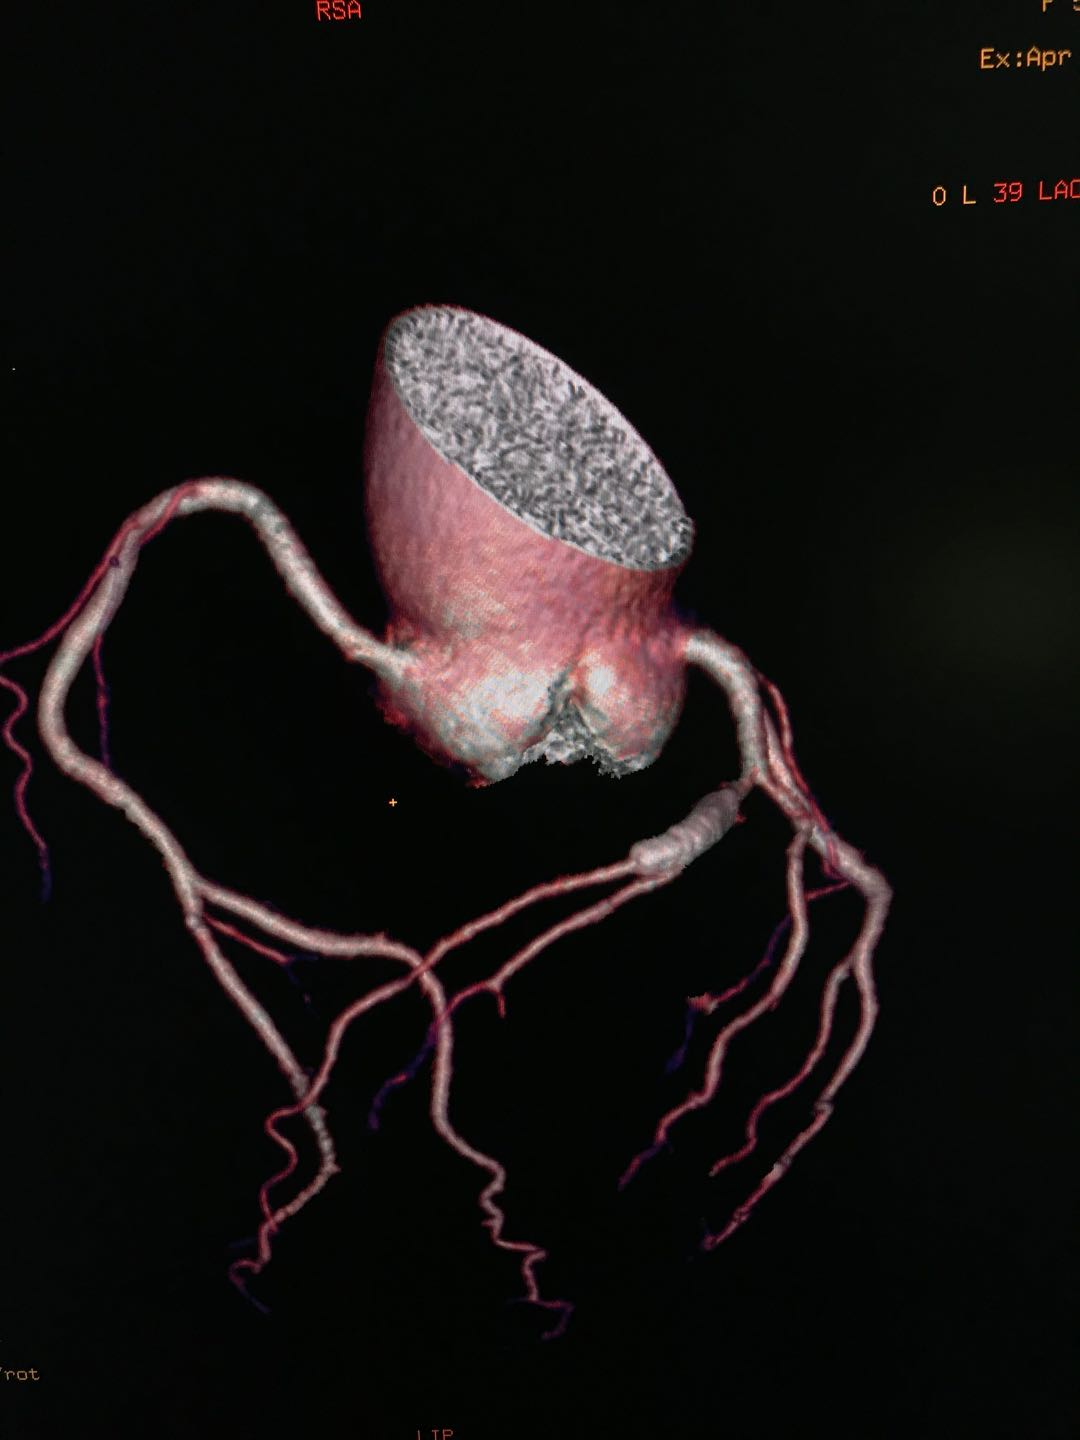

要想排除冠心病诊断,首选冠脉CTA 冠脉CTA检查,是一种特殊的增强CT扫描,只要图像清晰,诊断无误,排除冠心病诊断的准确率高达99%。除此以外,目前其他任何的心脏检查均不能排除冠心病的诊断。

冠脉支架植入术后或搭桥术后的复查

以往支架植入术后的复查需要再次做造影复查。现在应用冠脉CTA复查,简单方便。